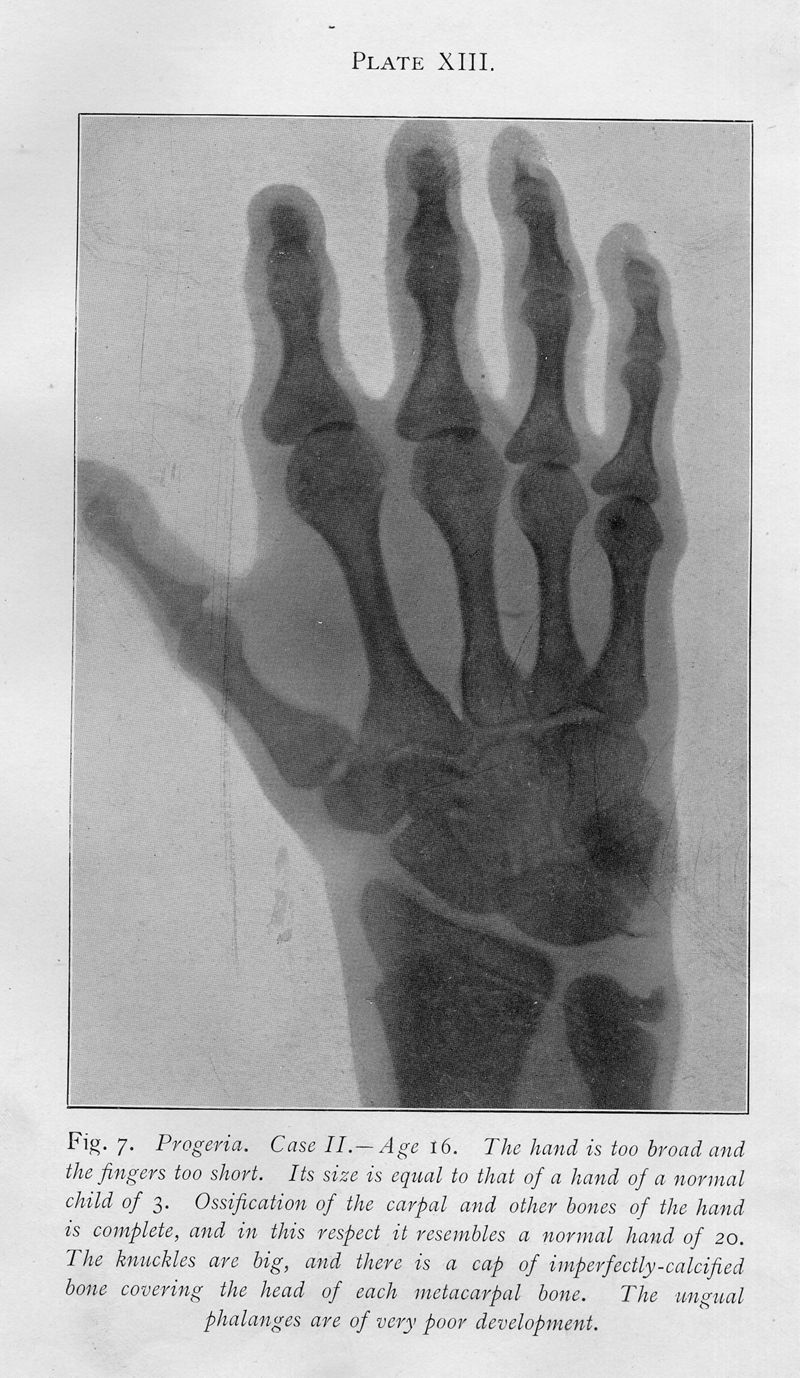

Progeria; a form of senilism

In : Practitioner, 1904, Vol. 73, pp. 188-217